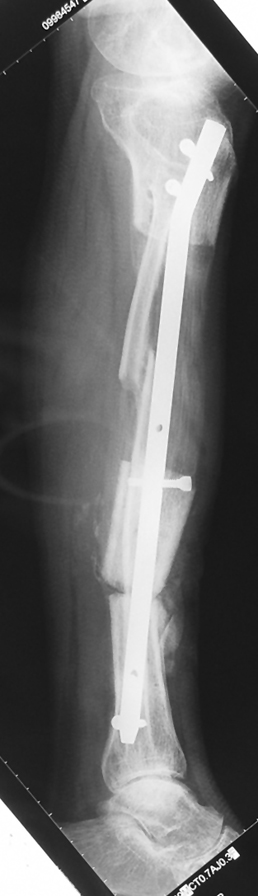

The duration of external fixation (external fixation index) depends on the amount of distraction required, and the extremity is prone to complications during this period. After the distraction phase is completed, the external fixator remains in place during the consolidation phase, which lasts twice as long as the distraction phase; but this period is hardly tolerated. If the external fixator is removed before sufficient consolidation is achieved, fractures, deformity and shortness will be the result. In our department, ‘lenghthening over nail’ method is used in order to decrease the external fixation index and increase patient comfort and activity level. In this method, the intramedullary nail is statically locked after the completion of the distraction phase, and external fixator is removed. The extremity is stabilized by the intramedullary nail during consolidation phase. In this way, complications due to long external fixation index or early removal of the external fixator are avoided.